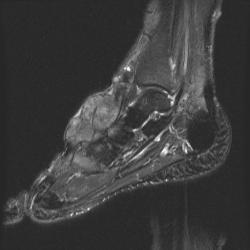

сагиттальная Т2

На серии МР-томограмм получены изображения правого голеностопного сустава.

На тыльной поверхности правой стопы, непосредственно под кожей в области таранной, ладьевидной, клиновидных и оснований от первой до третьей плюсневых костей определяется патологическое образование (тофусы), с распространением на медиальную поверхность стопы, образование неоднородной структуры и МР-сигнала, умеренно гиперинтенсивное на Т1 ВИ, гипоинтенсивное на Т2 ВИ и неоднородного на FAT SAT ИП. Размеры образования 35 х 65 х 40 мм. На постконтрастных изображениях отмечается значительное диффузное усилением интенсивности МР-сигнала от образования. Аналогичные по МР-характеристикам образования, меньших размеров выявляются в левой стопе.

Со стороны костной системы определяются: единичные костно-хрящевые дефекты со склерозом по периферии, диаметром до 3 мм, располагающиеся в субхондральных отделах в области суставных концов большеберцовой и малоберцовой костей, в области прикрепления длинной подошвенной связки к подошвенной поверхности пяточной кости. Множественные дефекты диаметром до 9 мм расположены в области смежных поверхностей ладьевидной и клиновидных костей, некоторые кистовидные дефекты вскрылись в мягкие ткани.

В пяточной кости правой стопы, определяется округлая зона повышенной интенсиновсти МР-сигнала на всех импульсных последовательностях в области блока малоберцовой кости, размерами 7 х 8 мм.

Суставные поверхности уплощены, суставные щели резко сужены, местами определяются краевые костные разрастания.